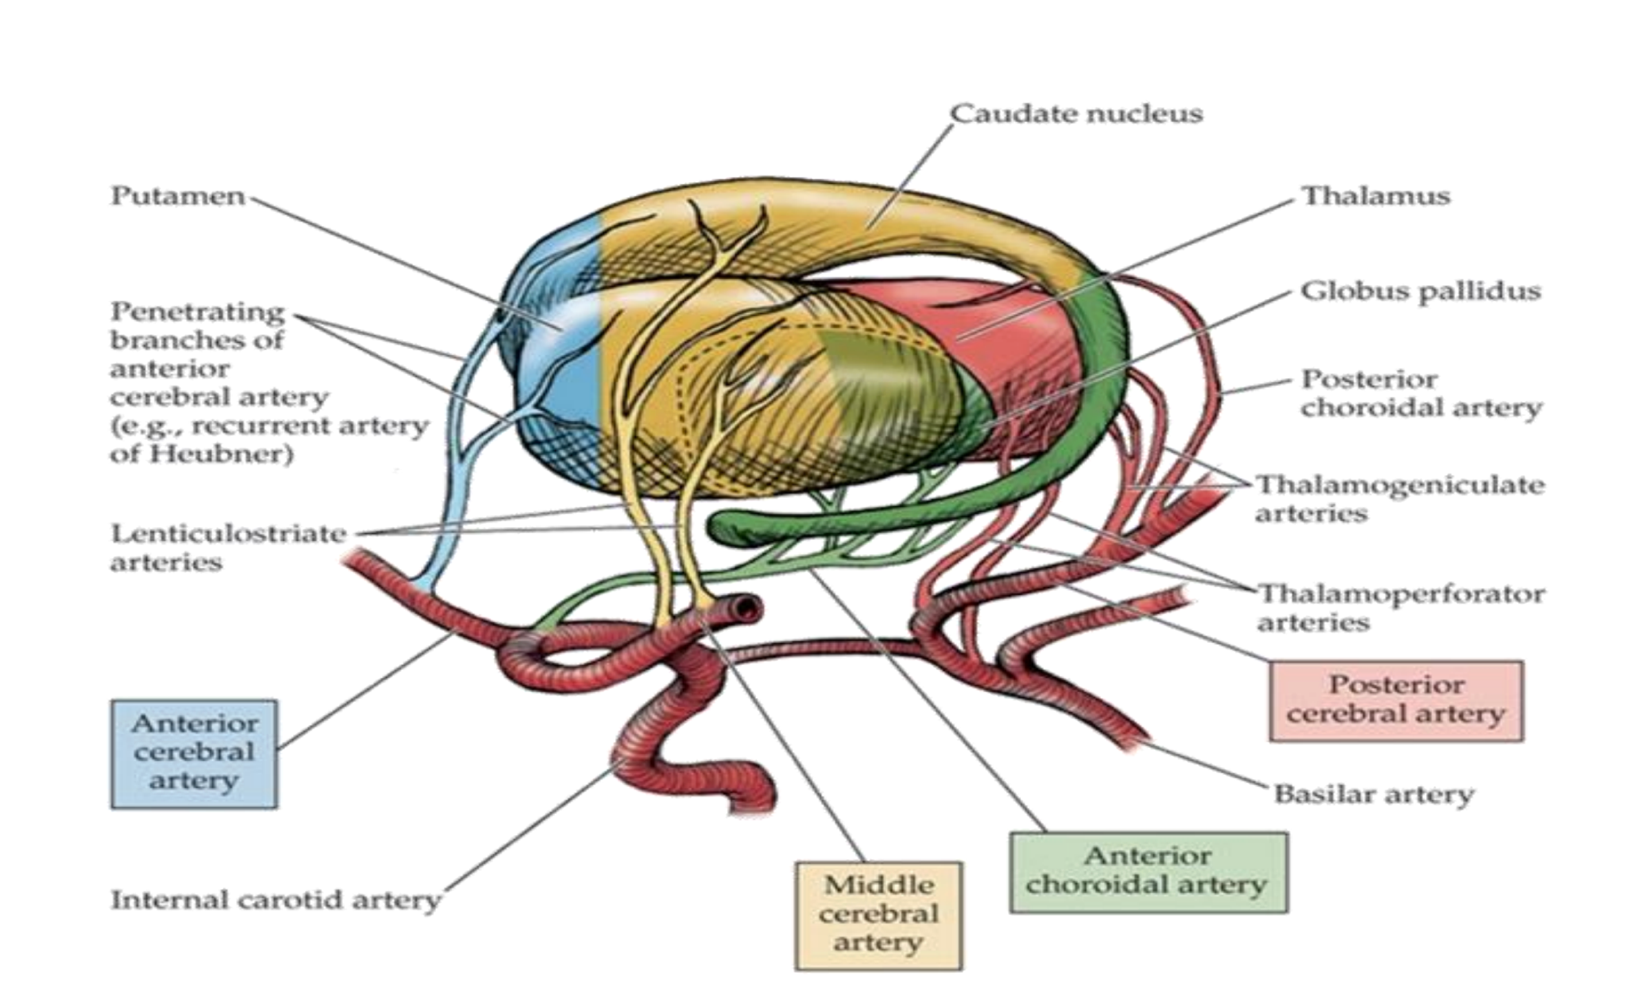

What supplies blood to the caudate nucleus?

Branches from anterior cerebral artery (anterior part)

Boddy of the middle cerebral artery

Tail of the anterior choroidal artery.

What supplies blood to the putamen?

Middle cerebral artery

Branches from anterior cerebral artery (anterior part)

What supplies blood to the globus pallidus?

Lenticular striate arteries

Anterior choroidal of internal carotid & internal capsule

What supplies blood to the thalamus?

Lenticulostriate arteries from the middle cerebral artery